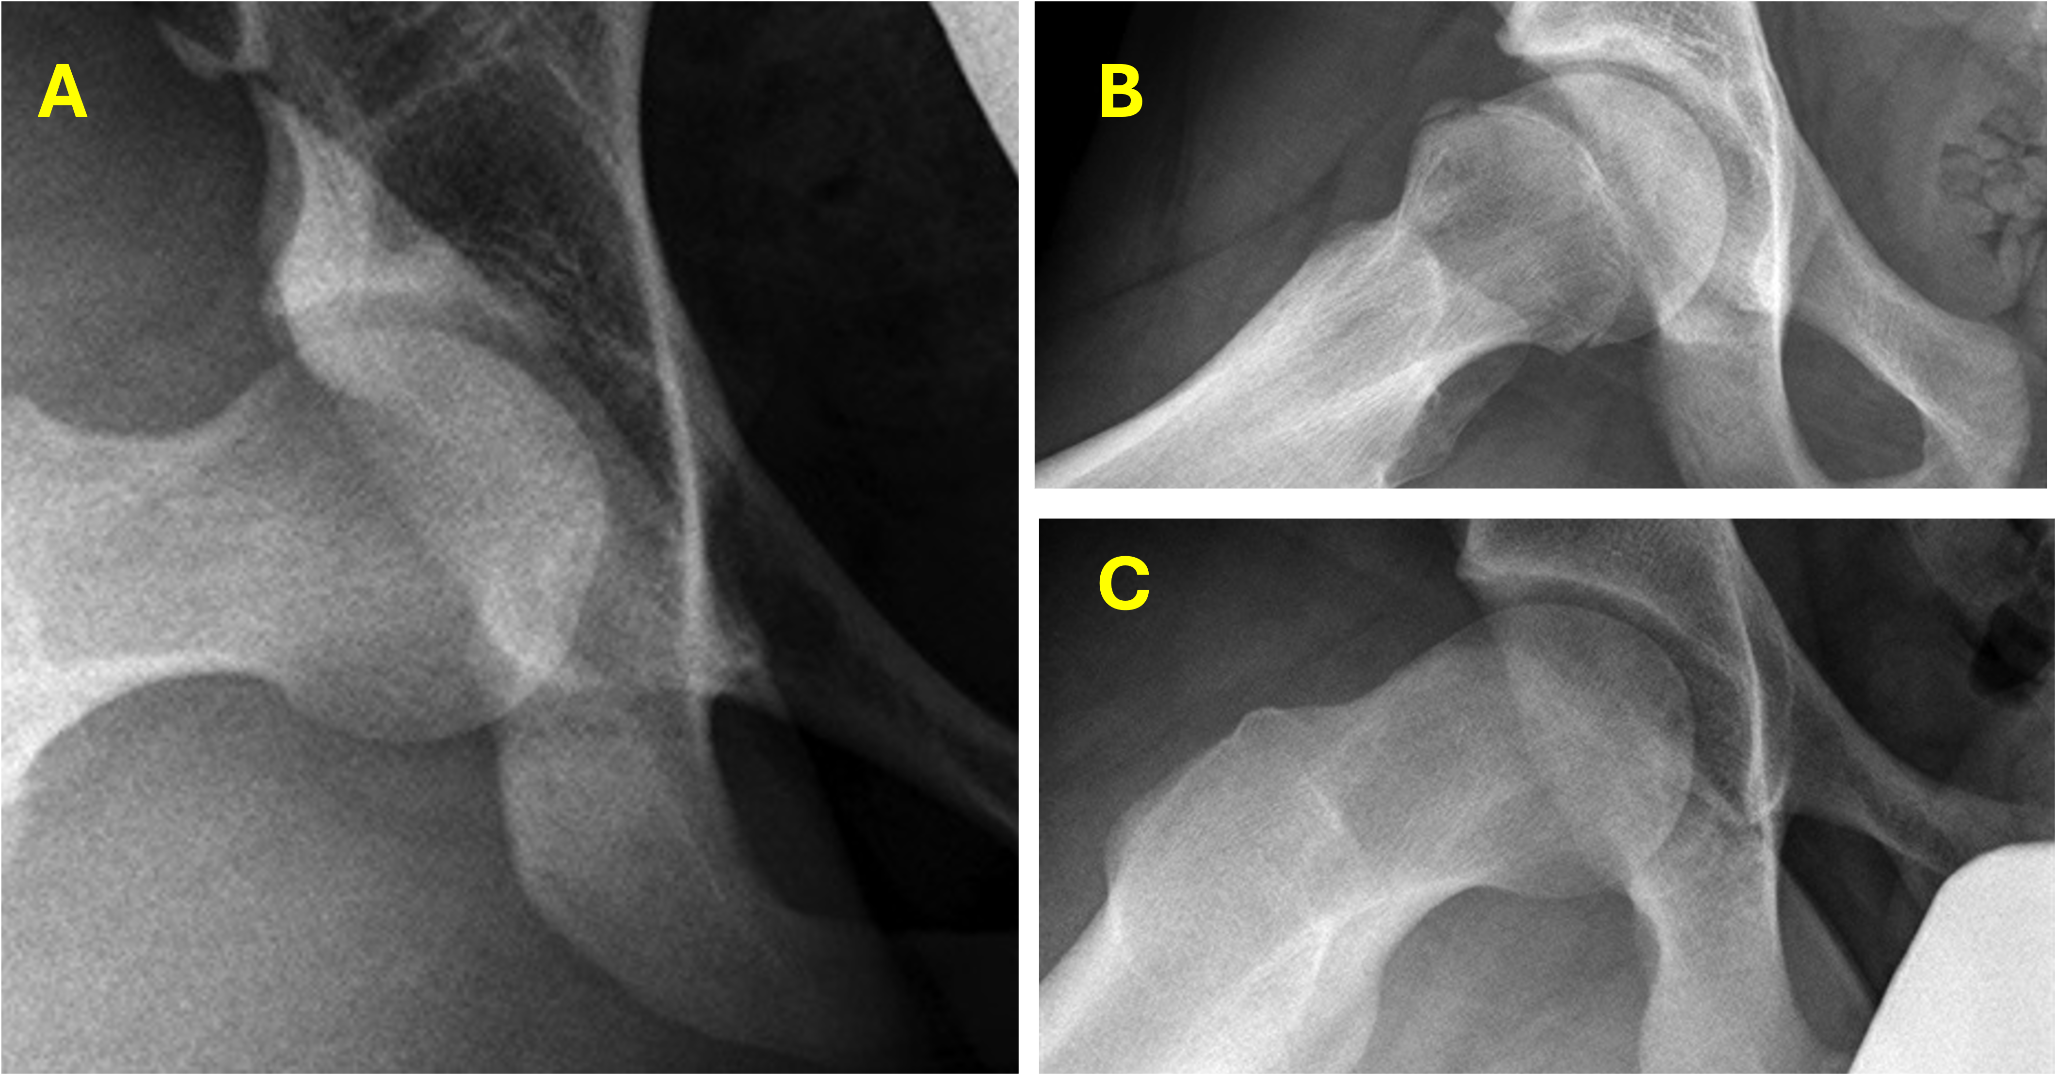

Three studies investigated the prevalence and characteristics of FAI morphology in patients with axSpA [11, 13, 27]. Lee et al. observed FAI morphometry in 36.7% of AS patients, with pincer-type being most prevalent (20.6%), followed by combined-type (9.6%) and cam-type (6.5%). The FAI group demonstrated a male predominance (87.2%) and significantly higher sacroiliitis scores compared to non-FAI patients [10]. Combined-type FAI correlated with the highest sacroiliitis scores [11]. Tosun et al. specifically examined cam-type deformity, reporting a higher prevalence of pistol grip deformity in axSpA patients versus controls (20.3% vs. 8.8%, p = 0.002) [20]. They identified significant associations between pistol grip deformity and male sex, smokers, and hip arthritis presence. Seth et al., while not focusing exclusively on axSpA, identified a unique “inflammatory beak” cam morphology (Fig. 2) in 8.9% of paediatric FAI patients with various inflammatory conditions, including AS [17]. This morphology was characterised by a negative femoral head-neck offset and increased alpha angles [28].

Fig. 2

The radiographic images demonstrate three distinct hip presentations. (A) normal hip morphology without symptoms, (B) a symptomatic hip displaying noninflammatory cam changes, and (C) a hip exhibiting the characteristic inflammatory beak formation of the cam deformity, which is frequently observed in patients with underlying inflammatory conditions [12]

The morphological observations reported by Seth et al. merit particular attention in the context of phenotypic variations across different patient populations. Their identification of a distinct cam morphology in paediatric patients with inflammatory conditions, characterised by a ‘sharp-edged’ head-neck junction, negative femoral offset, and increased alpha angles, represents a potentially significant radiological finding. This unique morphological pattern may serve as an important diagnostic indicator when evaluating young patients with hip pain, particularly in the context of concurrent inflammatory conditions. While the pathophysiological basis for these distinct morphological features remains to be elucidated, their recognition contributes to our understanding of the heterogeneous manifestations of hip pathology and underscores the importance of comprehensive radiological assessment in different patient subgroups.